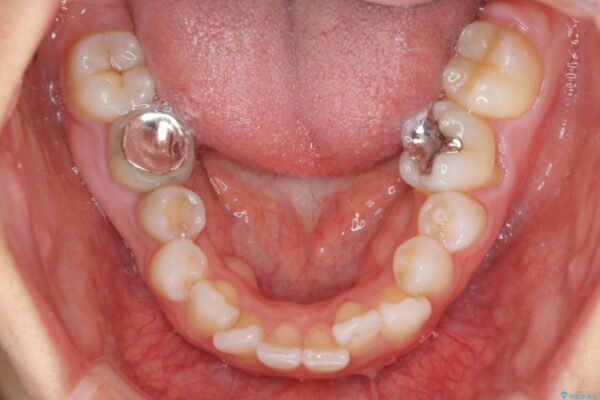

口元の閉じにくさと、奥歯の咬み合わせを気にして来院された患者様です。

左下の大臼歯2本が顕著に舌側に傾斜しているため、まずは奥歯の咬み合わせを改善をし、その後上下左右の第1小臼歯4本を抜歯することで口元を引っ込めながら整えることとしました。

治療前

• 【モニター】出っ歯と咬み合わせを改善 ワイヤー装置の抜歯矯正 治療前画像